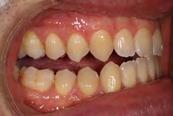

Clinical evaluation showed a mild Class III skeletal pattern with a constricted maxilla, mildly dolichofacial and straight

profile (Figure 1). Full adult dentition was present with all third molars extracted. Maxillary and mandibular incisors were normoclined. The maxillary midline coincided with the facial midline, and the mandibular midline was 2 mm to the right of the facial midline. There was a 2 mm to 5 mm lateral open bite on the right side from the second molar to the lateral incisor, and the maxillary occlusal plane was canted to the left of the interpupillary line. A lateral tongue thrust into the open bite was noted on swallow.

The right side was in posterior crossbite and there was an edge-to-edge anterior bite with wear on the maxillary central incisors. Mild gingival recession was noted, but soft tissue was generally within normal limits. CBCT analysis found no radiographic evidence of osteoarthritis in the TMJ joints, nor osseous or apical pathology involving the maxillary or mandibular teeth. His airway was not constricted. Initial report from the myofunctional therapist indicated that the patient never developed a mature swallow sequence and had a bilateral posterior tongue thrust.

Figure 1. Initial records.